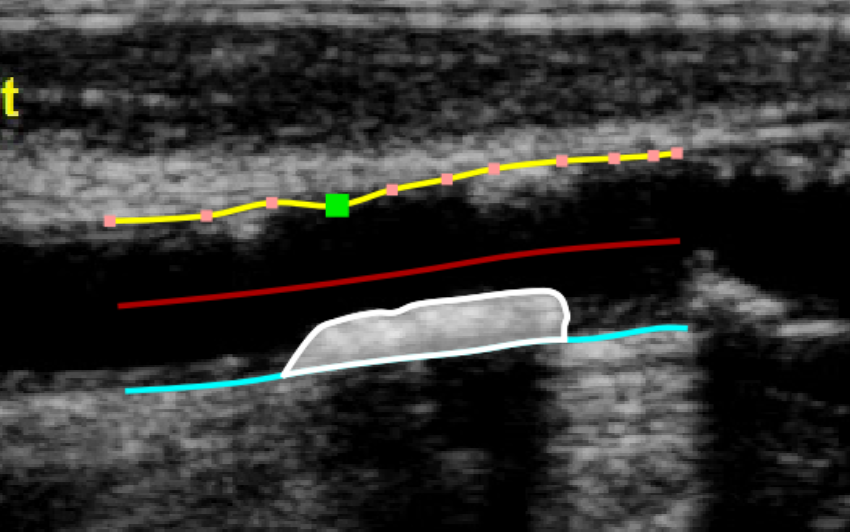

After the two borders are traced, the software automatically compute the minimum and maximum values of the diameter and the linear and circular values of the stenosis. The Draw plaque button is used to manually draw the profile of a plaque. The user has to trace point-by-point the plaque profile and the software interpolates them. Also in this case, it is possible to modify the points by dragging them and to delete a plaque, as shown in the following picture.

After the plaque is drawn, the software automatically computes its area, perimeter, and the mean, standard deviation, skewness, and kurtosis of its grey level. - Data panel